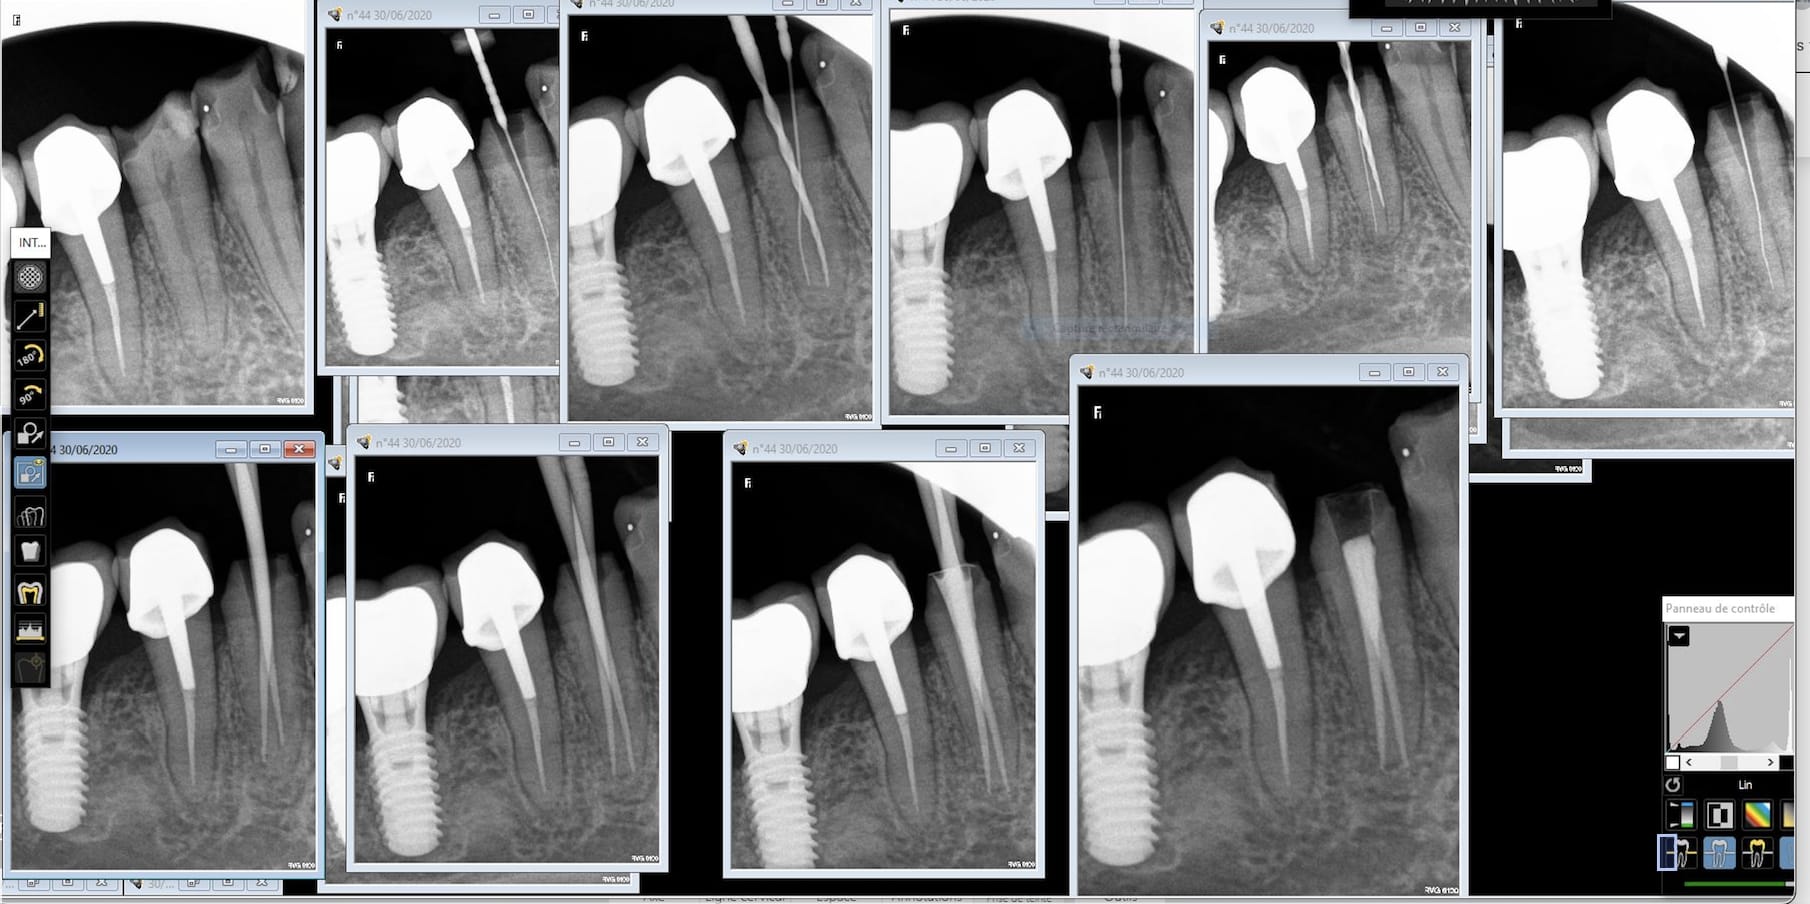

Ce matin reprise de traitement de 16 pour un ami qui habite la Suisse.

Un lentulo cassé dans la racine palatine, obturation sur 4 mm sur la mp et rien sur la dp.

C'était la rte en France ou extraction implant en suisse.

Et surtout formes toi auprès de ceux qui savent faire et qui nen font beaucoup avec des résultats reproductibles. En une semaine je dois faire les endos que fait un prof en 6 mois. -)

Pugilat mis à part, la difficulté de l'endo est surévaluée. A vu de nez, 90% se gèrent sans soucis si on bosse consciencieusement et bien équipé. Quand je vois une endo à mi racine et un canal d'un mm de diamètre qui continue jusqu'à l'apex sur une pano, pas besoin d'avoir vu 600 traitements pour faire mieux.

Reste 5% d'endos merdiques prévisibles à adresser, et 5% imprévisibles qu'il faudra identifier le plus tôt possible avant d'avoir fait une perfo ou pété une lime.

Tu le dis toi même, un bon praticien a des résultats reproductibles, et c'est pour moi plus une question de technique que d'expérience, même si cette dernière aide évidemment à acquérir la première.

Les endos pourris que je vois passer, c'est avant tout le résultat de praticiens qui s'en foutent.

Bon, chapeau pour la 2ème qui a une séparation des canaux assez basse qui a du être assez pénible à préparer et la négociation de la courbure de la 4ème. Les autres ont 2 canaux mais l'accès semblait relativement aisé et leur naissance assez haute pour qu'on ne puisse pas vraiment les rater.

Et très sérieusement et je pose la question car je me la pose vraiment, pour chacune de ces dents, est-ce que tu considères qu'elles ont été difficiles à traiter?

J'entends par là avec un risque d'échec (casse, oubli de canal, obturation incomplète, ...) élevé qu'un praticien lambda consciencieux qui aurait pris le temps nécessaire n'aurait pas sur gérer, et que toi tu as su gérer uniquement grâce à ton expérience (et tes formations peut être?) ?

Aucune, mais ça serait plus simple si à la base on t'apprenais à les faire correctement. -)